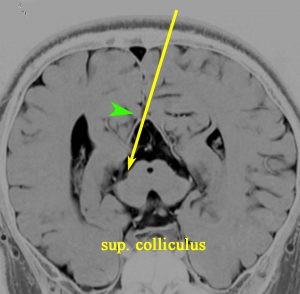

5. 後交連 PC posterior commissure

松果体腫瘍が上丘を圧迫して眼球運動障害を呈することは良く知られています。実際に松果体腫瘍の手術で上丘を損傷することはほとんどなく,術後に残る微妙な複視は,後交連 (PC posterior commissure) の損傷によって生じます。左の画像のように,松果体腫瘍が第3脳室方向に伸展増大すると後交連を圧排して,後交連は扁平化します。手術中には,上丘の奥に,上丘と連続して白く薄い脆弱な白質組織が見えます。それが後交連です。左右にも長い白質組織なので,腫瘍底面から非常に慎重に剥離する必要があります。後交連の剥離が終わると第3脳室内の髄液腔に抜けます。

左の図は,眼球運動に関わる中枢と神経を表したものですが,PTAの手術で損傷するのは,PC 後交連とSC 上丘くらいなもので,上丘は丈夫な組織なので,術後合併症である複視は後交連損傷であることが多いのです。